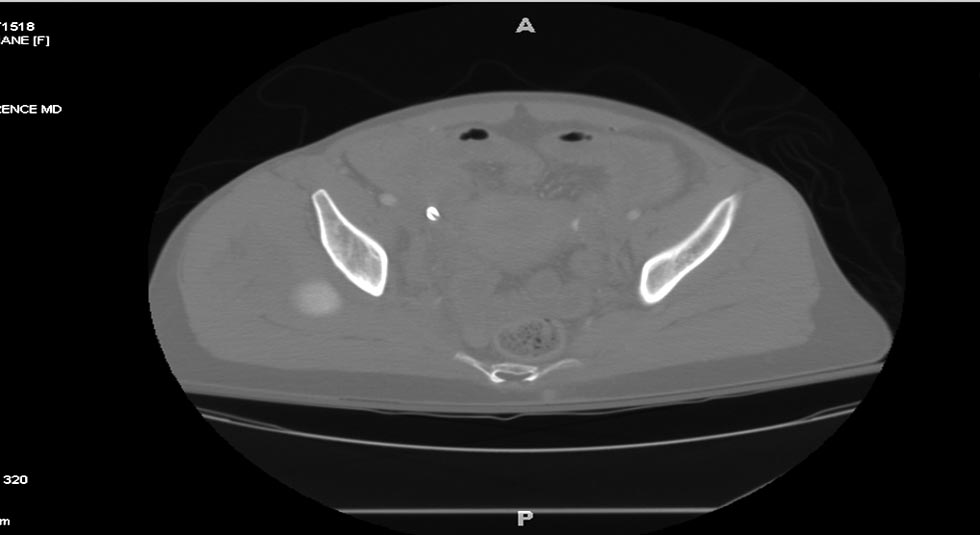

Травма хирург принял решение продолжать лечение в операционной. Срочная диагностическая лапаротомия с абдоминальной тампонадой, переливание 5 единиц крови. Irrigation & Debridement открытых ран с вакуумированием, попытка закрытой репозиции деформации сустава. По-прежнему состояние тяжелое, но давление стало стабилизироваться. Смогли получить первые диагностические данные.

Здесь перечислены ортопедические повреждения: Rt. femoral shaft fracture, Rt femoral head fracture-dislocation, Rt distal femur fracture, Rt. open patella fracture, Rt. talus fracture dislocation, Rt. open humerus fracture, Left 5th metatarsal fracture, Left dislocation 1st TMT.

Интенсивные реанимационные мероприятия продолжаются в ICU, на следующий день сделана Irrigation &Debridement раны живота с последующим ушиванием серозной оболочки, наружный фиксатор на правое бедро. В связи со стабилизацией состояния получили добро на короткую операцию. Каккое из повреждении является более приоритетным? С чего начать?